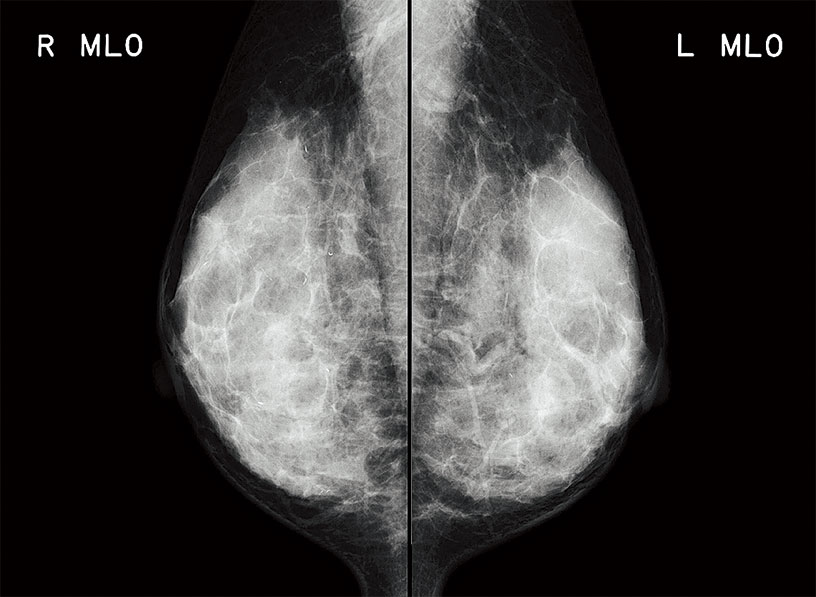

For the first time in the PRIMA series, the model is equipped with a mammography image reading function. With high definition reading and the fastest processing in the tabletop class, this model brings about a seamless workflow to your diagnosis.

With the highest processing speed in its class, this model can process 73 images per hour. In addition, 40 mammography images can be processed within an hour, allowing smooth image reading.